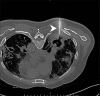

Utility of 2-Deoxy-2-[18F]fluoro-Dglucose positron emission tomography/computed tomography scan in the systemic evaluation of patients with post-COVID-19 endogenous presumed fungal endophthalmitis

Keywords: CT scan; FDG PET/CT; endophthalmitis; mucormycosis.